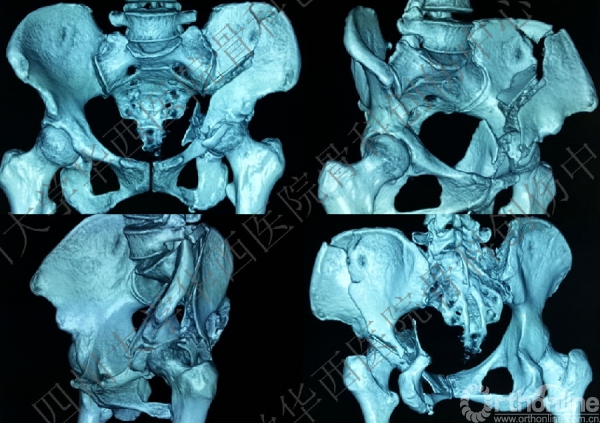

术前三维CT

做三维重建,进一步为手术做术前详细的计划,决定前方入路。